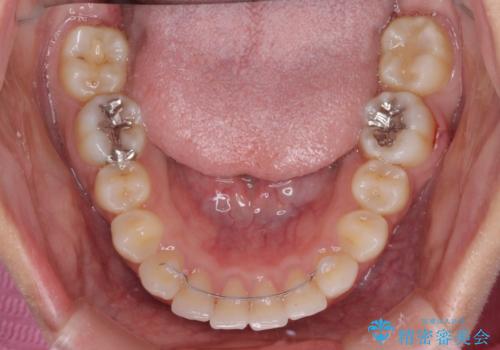

もう少しデコボコを改善したかったのですが、ご本人の希望もあり、装置を除去しました。

後戻りを防止するため、舌側を細いワイヤーによる保定を行いました。